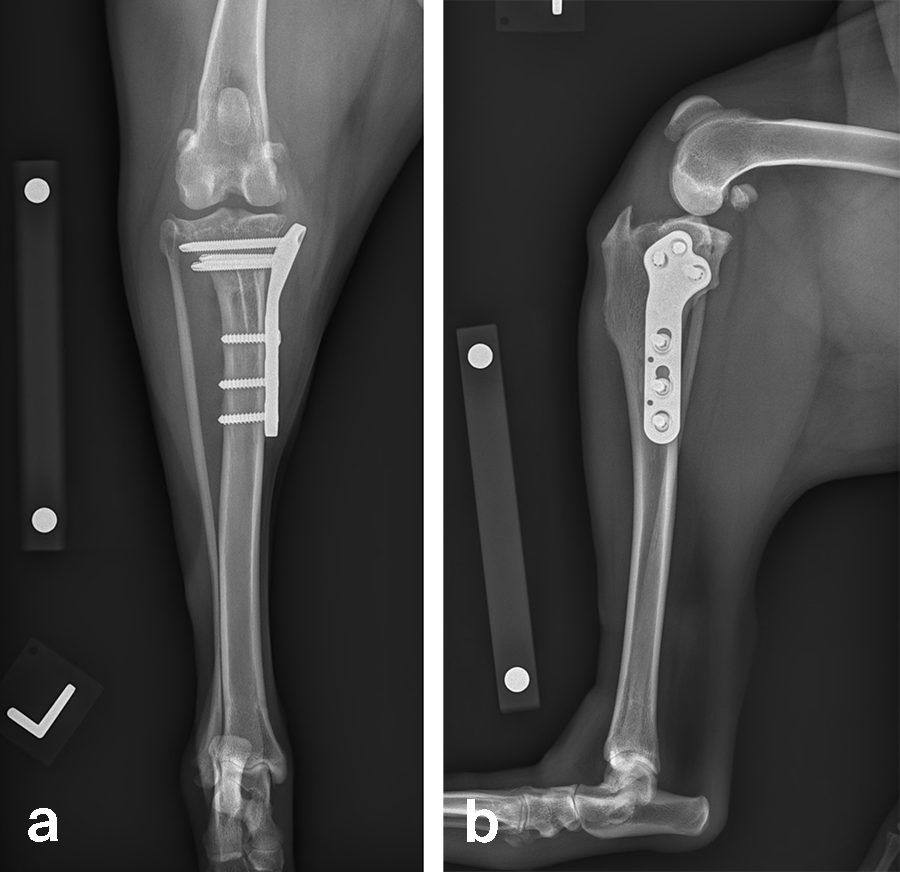

A 32 kg male neutered Golden Retriever presented with a recent deterioration of chronic right hind limb lameness. Physical examination revealed a cranial cruciate ligament rupture.

Follow-up x-rays at 8 weeks postoperatively revealed stable implants, stable bone segments, and healing of the osteotomy. The clinical outcome was satisfactory.